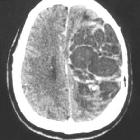

zystisches Astrozytom

Astrozytom RadiopaediaCC-by-nc-sa 3.0de